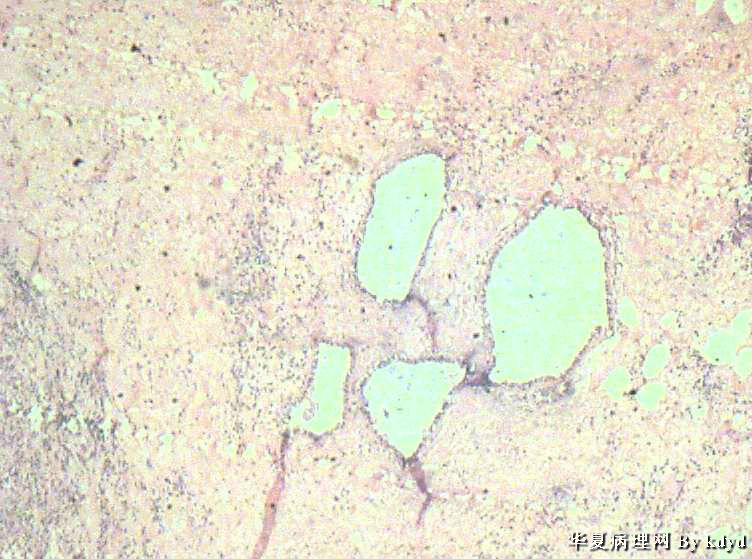

B3997左乳肿瘤--浸润性导管癌?

37岁,女。左侧乳腺肿块发现5个多月,伴隐痛。

手术见:肿块与周围组织分界不清,无明显包膜。

大体:不整形组织大小约3.5*35*2CM,未见明显包膜。质较软,切面浅黄色,一侧见一小囊腔直径约0.8CM囊壁较粗糙。

标签:乳腺浸润性导管癌 原位癌

浸润性乳腺导管癌?

IDC

乳腺浸润性导管癌

囊壁内大量炎细胞浸润,囊壁被覆细胞有明显异型,可见核分裂,考虑癌,不知有无陷阱

浸润性导管癌

应该是个浸润性导管癌

但是,片子质量欠佳

不太敢直接下

诊断乳腺浸润性导管癌确实有些担心,制片质量确实要提高,制作优良的切片,是正确诊断的前提。